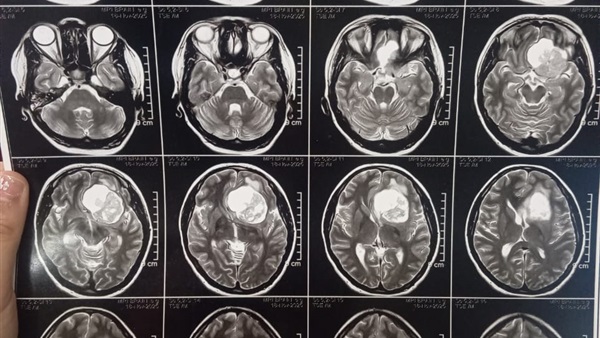

ومن جانبه، أوضح الدكتور مجدي القاضي عميد كلية الطب البشري ورئيس مجلس إدارة المستشفيات الجامعية أن المريضة حضرت وهي تعاني من صداع شديد وارتفاع بضغط المخ مع تدهور ملحوظ في حدة الإبصار، وبإجراء الفحوصات الطبية اللازمة وأشعة الرنين المغناطيسي، تبيّن وجود ورم كبير بقاع الجمجمة ضاغط على أعصاب البصر والأوعية الدموية المغذية للمخ، ما استدعى التدخل الجراحي العاجل باستخدام أحدث التقنيات الدقيقة.